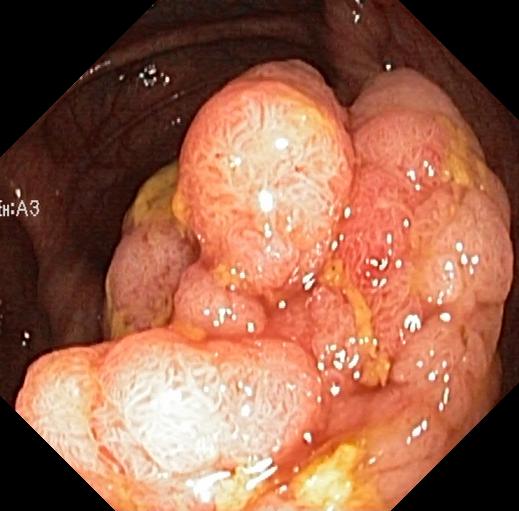

where NVsubscript𝑁𝑉N_{V} is the number of pixels covered by the lens in an image at its original size, y^i,jsubscript^𝑦𝑖𝑗\hat{y}_{i,j} is the value in the post-processed prediction for the jthsuperscript𝑗𝑡j^{th} pixel covered by the lens in the ithsuperscript𝑖𝑡i^{th} image at its original size, and yi,jsubscript𝑦𝑖𝑗y_{i,j} is the corresponding target value. For all metrics, a lower value indicates better performance. The results are presented in Table IX, and some examples are shown in Fig. 3 with corresponding error maps shown in Fig. 4 to help visualise the differences.

Input Target RN-HK-MC RN-HK-BT RN-IN-MC RN-IN-BT RN-IN-SL RN-NA-NA Refer to caption Refer to caption Refer to caption Refer to caption Refer to caption Refer to caption Refer to caption Refer to caption Refer to caption Refer to caption Refer to caption Refer to caption Refer to caption Refer to caption Refer to caption Refer to caption Input Target VT-HK-MC VT-HK-MA VT-IN-MC VT-IN-MA VT-IN-SL VT-NA-NA Refer to caption Refer to caption Refer to caption Refer to caption Refer to caption Refer to caption Refer to caption Refer to caption Refer to caption Refer to caption Refer to caption Refer to caption Refer to caption Refer to caption Refer to caption Refer to caption

Figure 3: Targets and post-processed predictions for a randomly selected instance from each of the test videos for C3VD. For conciseness, we denote ResNet50s with RN, ViT-Bs with VT, Hyperkvasir-unlabelled with HK, ImageNet-1k with IN, MoCo v3 with MC, Barlow Twins with BT, MAE with MA, supervised pretraining with SL, and no pretraining with NA-NA.